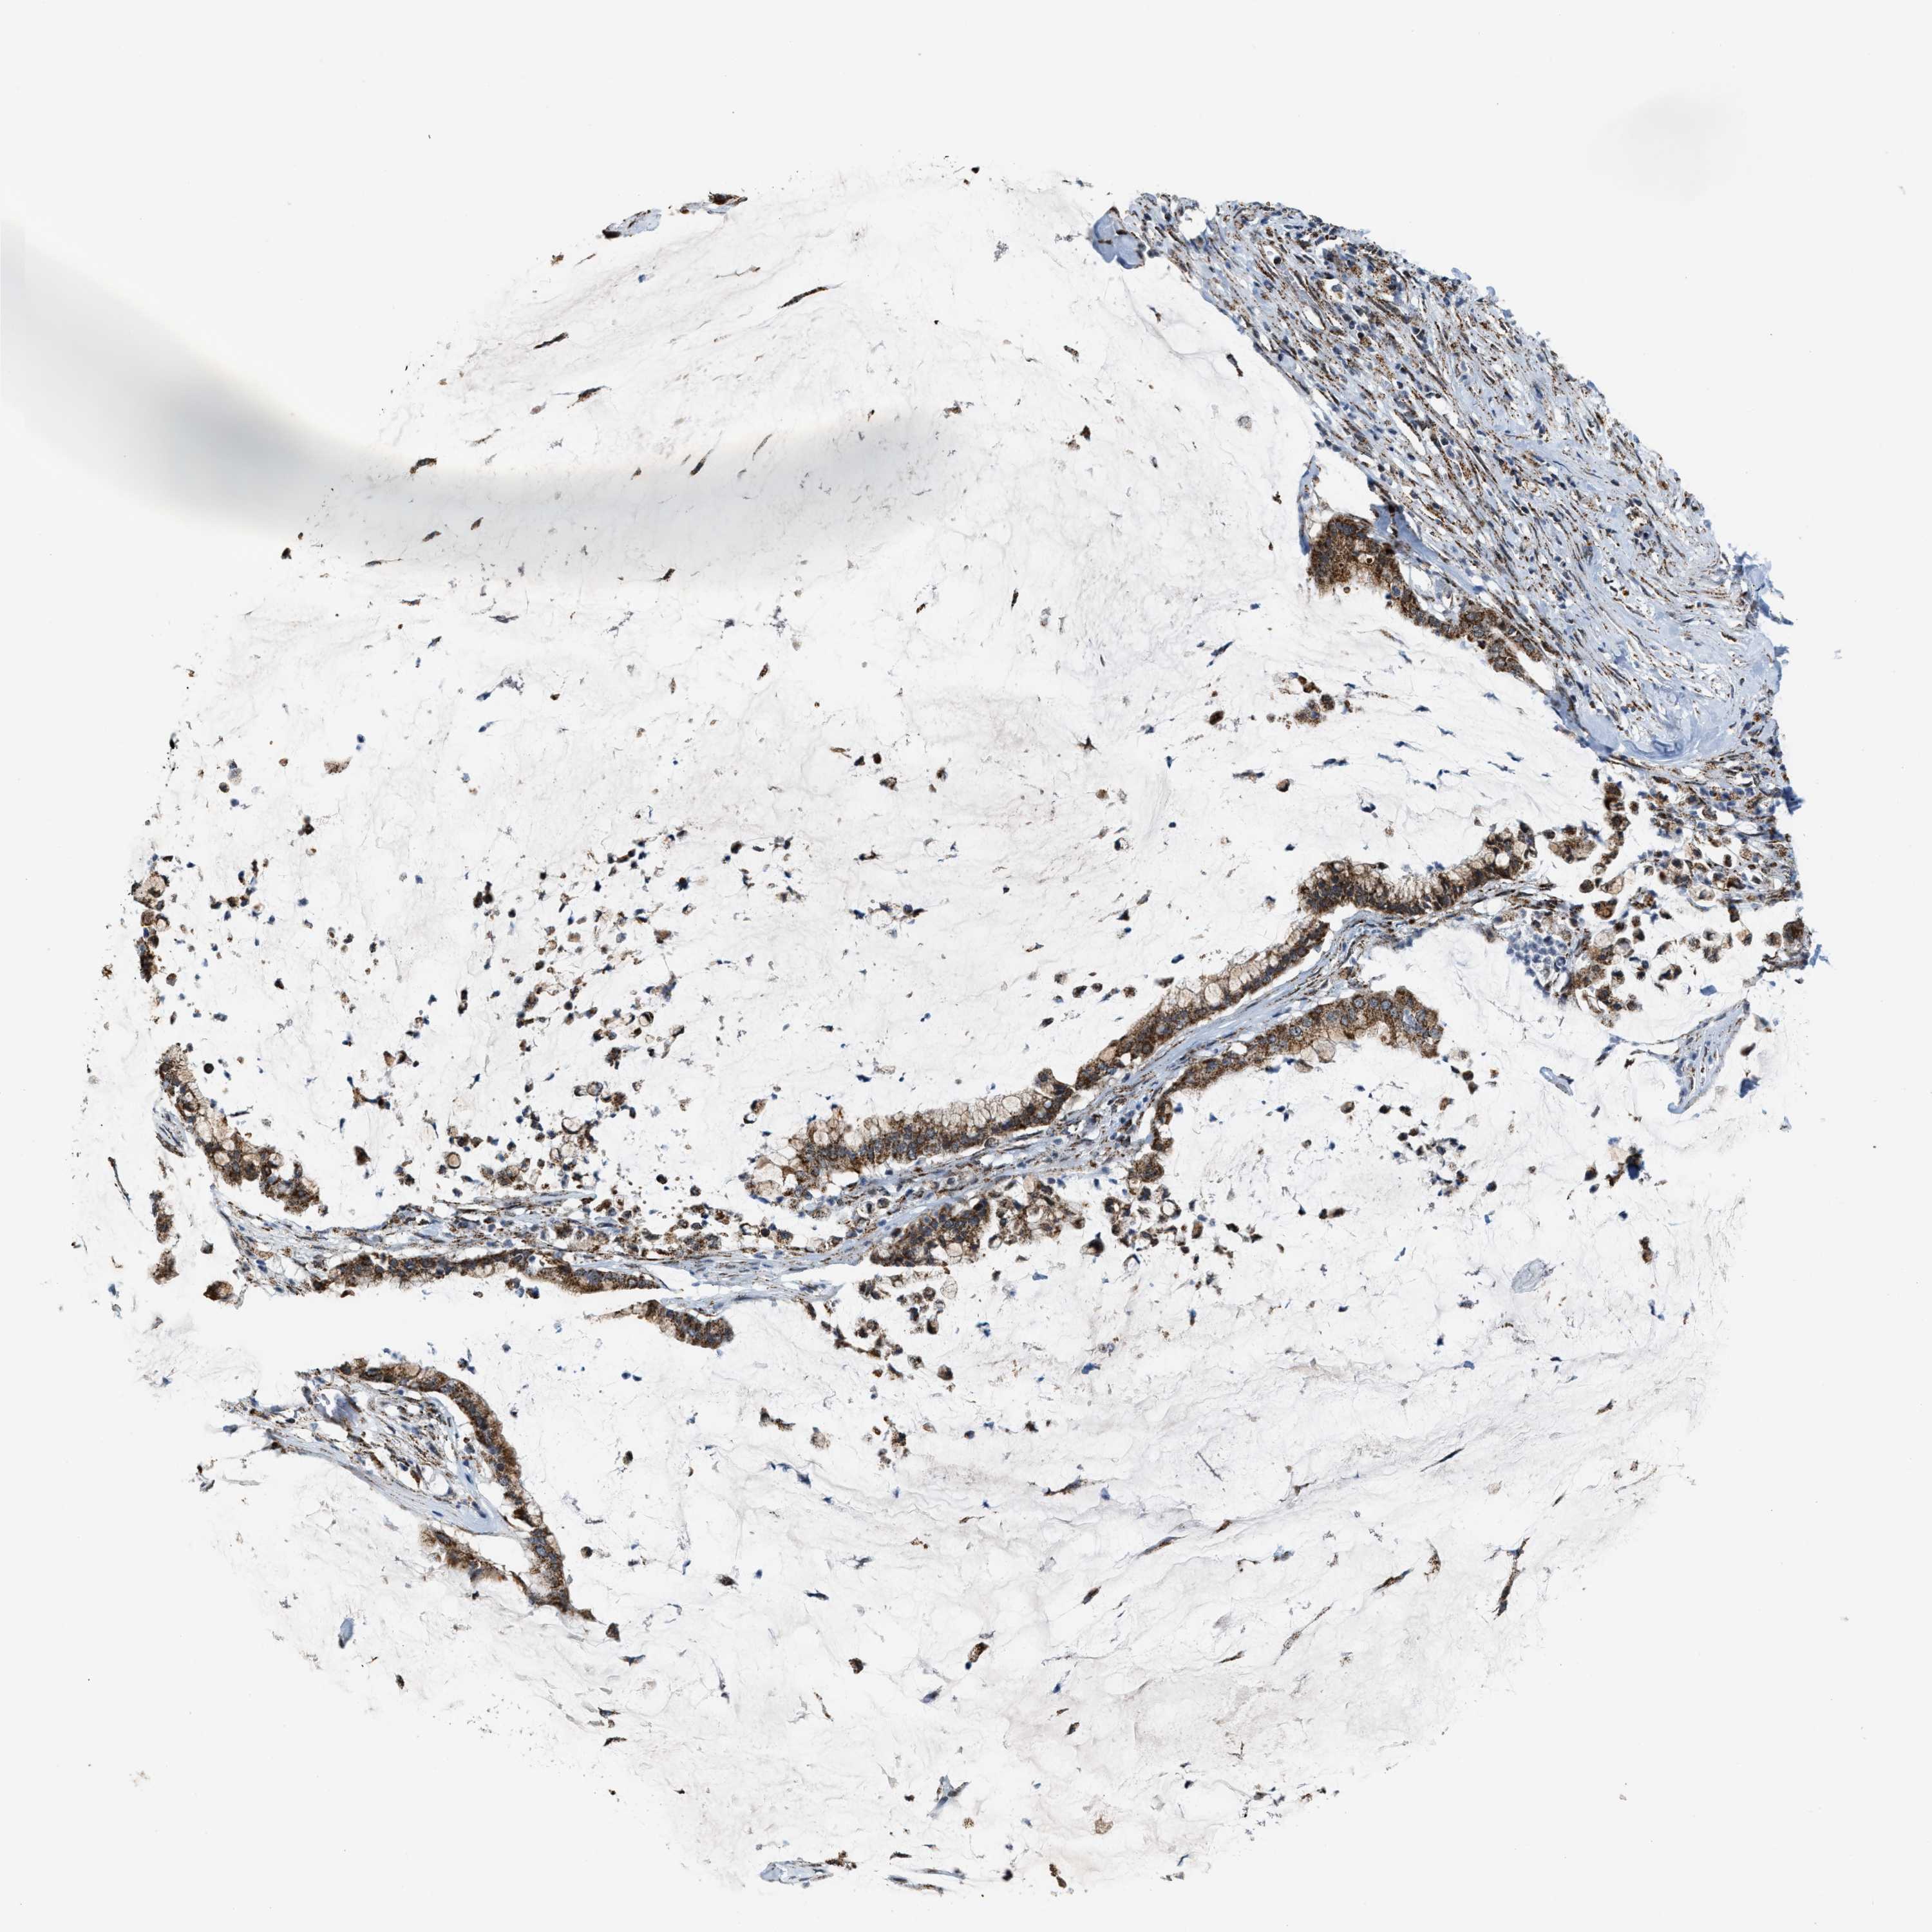

PANCREATIC CANCER - Protein expressioni

A mouse-over function shows sample information and annotation data. Click on an image to view it in a full screen mode. Samples can be filtered based on level of antibody staining by selecting one or several of the following categories: high, medium, low and not detected. The assay and annotation is described here.

Note that samples used for immunohistochemistry by the Human Protein Atlas do not correspond to samples in the TCGA dataset.

Antibody stainingi

Antibody staining in the annotated cell types in the current human tissue is reported as not detected, low, medium, or high, based on conventional immunohistochemistry profiling in selected tissues. This score is based on the combination of the staining intensity and fraction of stained cells.

Each image is clickable and will lead to virtual microscopy that enables deeper exploration of all samples and also displays staining intensity scores, fraction scores and subcellular localization as well as patient and tissue information for each sample.

Antibody HPA019522

Antibody HPA021002

Adenocarcinoma, NOS